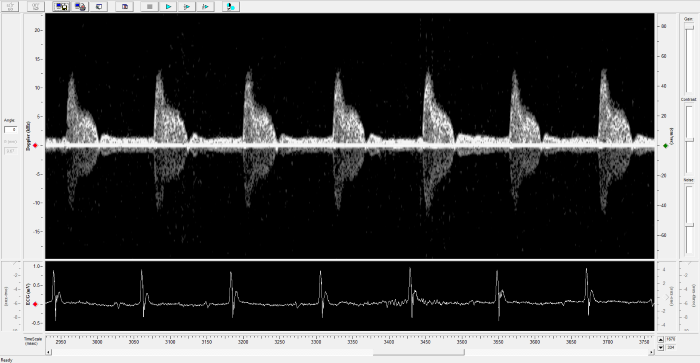

Imaging gallery - Doppler Flow Velocity System

Carotid Image. Image Credit: Scintica Instrumentation Inc.